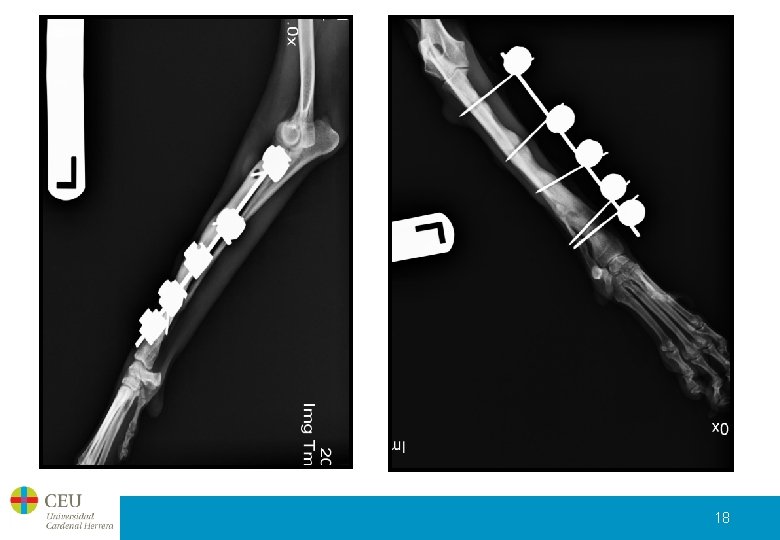

Control post-quirúrgico El pasado jueves 14 de enero, tras dos meses de evolución desde la segunda intervención que se realizó se le retiraron todos los implantes a Cuca. Presenta una evolución muy favorable, la perra está perfectamente y el hueso más que consolidado. A continuación podemos ver las radiografías que se le hicieron antes de quitar los implantes del fijador externo y una vez quitados. 17

18